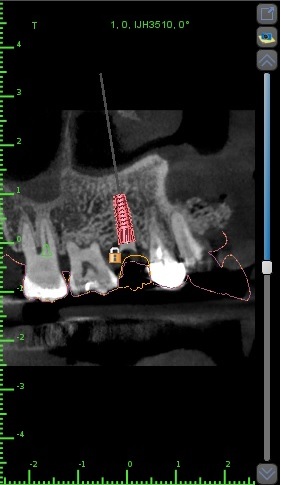

所以我們皆會使用手術導板

先在電腦上設計好植牙位置、角度

避開危險區域

(上顎的話就是鼻竇)

(下顎的話為神經)